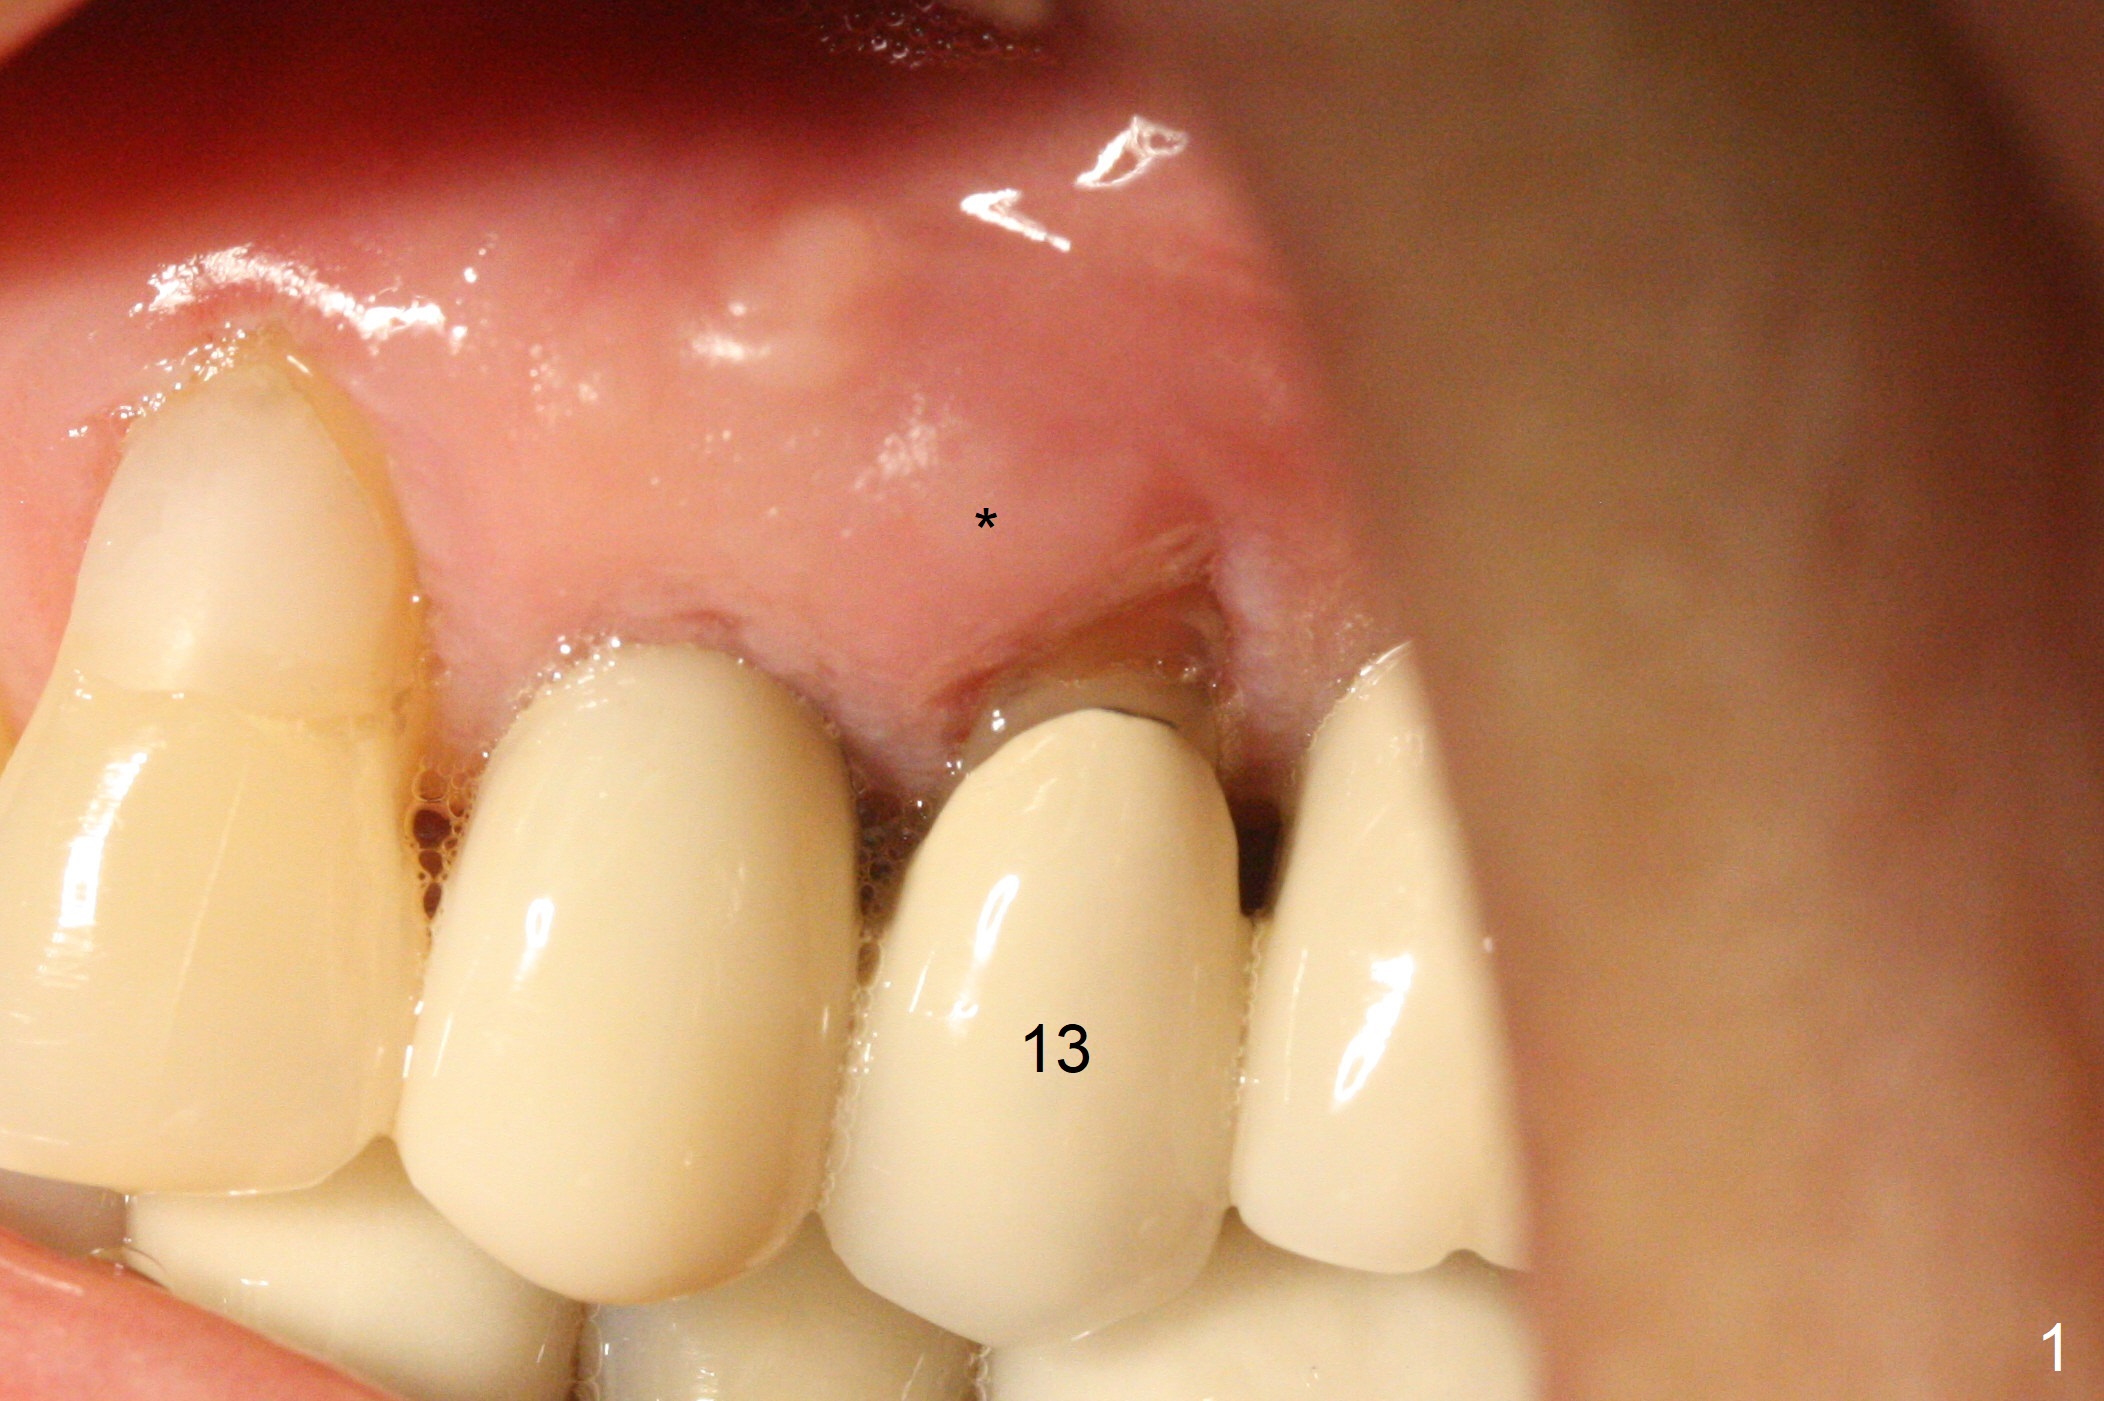

A 59-year-old woman has mild discomfort in the upper left quadrant, which is alleviated by salt water rinse. The buccal gingiva recedes at #13 with mesiobuccal swelling and deep pocket (Fig.1,3), corresponding to the mesial radiolucency (Fig.2 *). The tooth appears to have vertical fractured root, as related to the retention post. Since the root tip curves distal, the initial osteotomy (Fig.5 red) should be established in the mesioapical slope after extraction (black). Following initial entrance, the trajectory will be changed to the long axis of the space (Fig.6) with PA to be taken. Measure the depth of the buccal crest against the buccal, proximal and palatal gingival margins. Place an implant, the same as #12 (4.5x20 mm) unless the mesiobuccal defect is extremely large (UF).